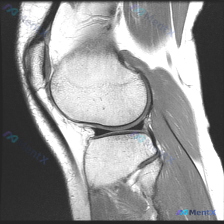

今天整理了一例踝关节MRI软骨异常的读片资料,分享一下我的分析思路,大家一起探讨。 病例基础信息 本次读片基于一张踝关节矢状位T1加权MRI图像,图像质量良好,解剖结构清晰,扫描范围涵盖胫骨远端、距骨、跟骨、舟骨及跗骨间关节。 影像核心发现 1. 整体正常表现:各骨骨髓信号均匀,无异常信号减低;骨皮...

踝关节MRI读片病例分享,整理了完整分析思路 这是一例踝关节矢状位T2加权MRI,我把影像发现和分析思路整理出来,和大家一起讨论。 一、基本影像信息 这是踝关节MRI T2序列矢状位图像,可观察到胫骨远端、距骨、跟骨及周围软组织结构,核心阳性征象如下: 1. 骨骼关节改变:距骨穹窿(圆顶)可见明确局...

刚看到一份足踝部矢状位MRI的影像资料,病灶特征很典型,整理一下病例和我的分析思路,和大家交流。 病例核心影像信息 这是T2加权或质子密度加权脂肪抑制序列的MRI,主要发现如下: 1. 核心病灶:距骨体部内部可见一个圆形/类圆形、边界清晰的高信号影,周围伴有低信号环,是典型的骨内病灶 2. 其他结构...